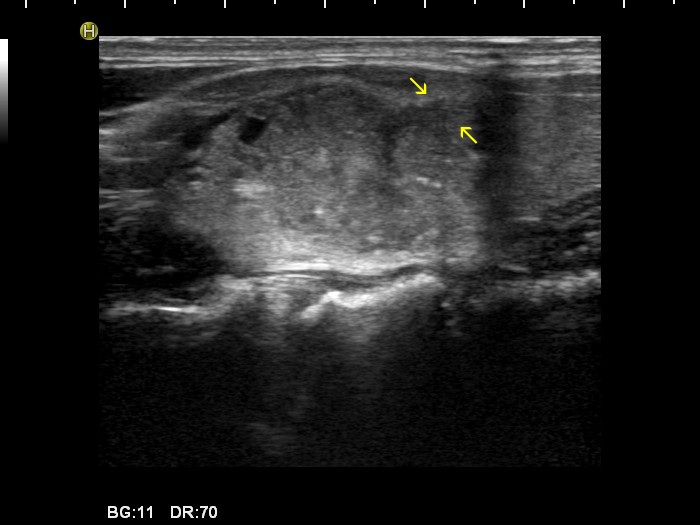

Papillary carcinoma (histology) - case 2082

Transverse scan

Longitudinal scan

In this case almost the entire border of the nodule is ill-defined, moreover the lesion has lobulated (yellow arrows) and spiculated (red arrows) margins, as well.